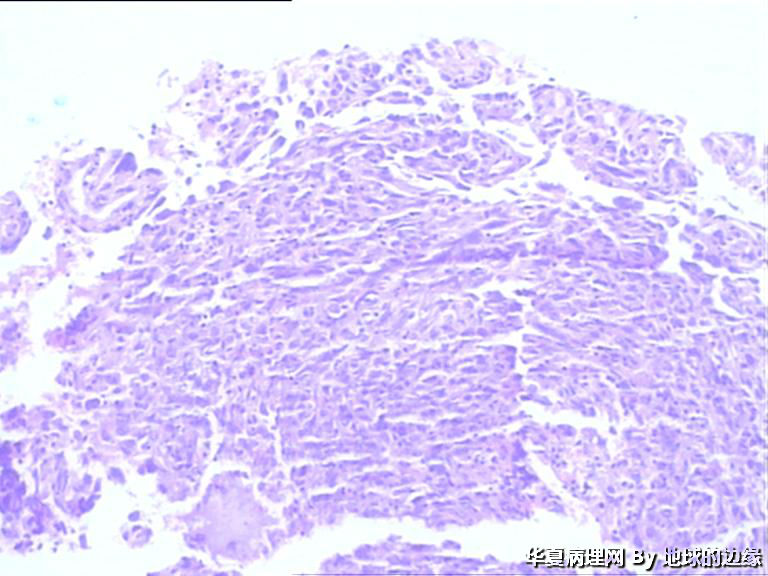

病人女性,48岁

MRI示:右肱骨肿瘤待排,包块大小为10x8cm,活动度差,边界欠清,鱼肉组织(白色),肿块侵犯至骨外    组  织。

恶性。是转移还是原发,是骨肉瘤还是浆母?需要进一步资料并标记。

考虑肉瘤,转移癌也排除一下吧

目前Vimentin阳性,P53阳性,AFP,EMA,CK7,CK20,E-ca,CR,PLAP,CD99,ER,PR,CEA,均阴性,只是没做淋巴瘤这一套了